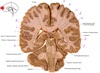

23

Q

a

septum pellucidum

24

b

Body of lateral ventricle

25

c

Corona radiata

26

d

Column of fornix

27

e

Third ventricle

28

f

Anterior commissure

29

g & h

amygdala (nuclear complex)

30

i

globus pallidus internus

31

j

globus pallidus externus

32

k

Putamen

33

L

Internal capsule genu

34

m

head of caudate nucleus

35

n

Anterior tubercle of thalamus

36

o

Body of corpus callosum